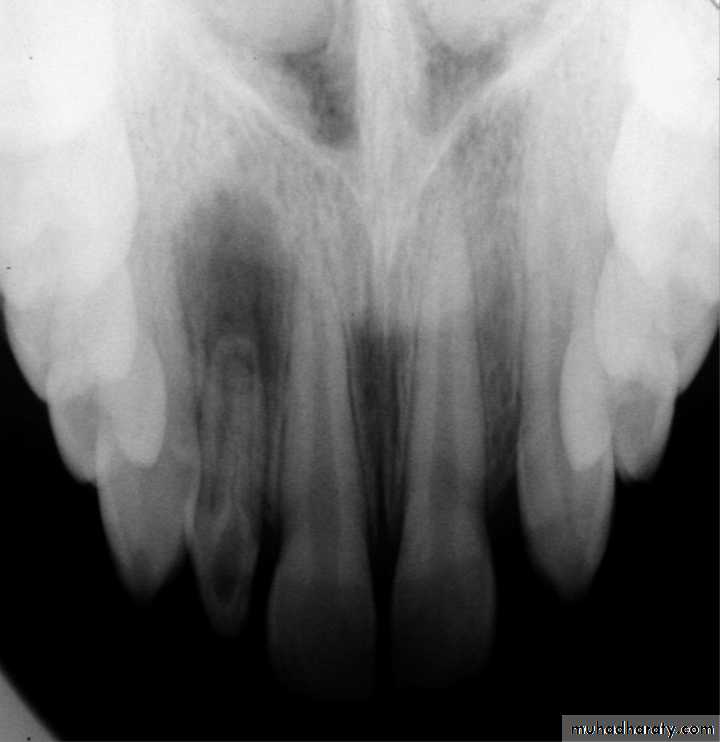

1. increase in number (Supernumerary tooth or hyperdontia)Rudimentary supernumerary, conical form.

HYPERDONTIA OR SUPERNUMERARYReasons :

• continue budding of enamel organ

• the cells become more fully differentiated and detached from the enamel organ